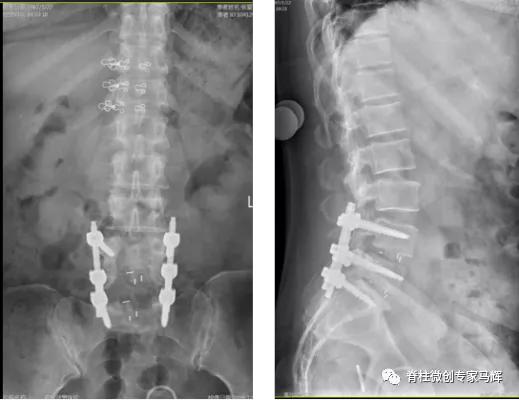

2018年腰椎术后

2019年腰椎内固定取出后

术后